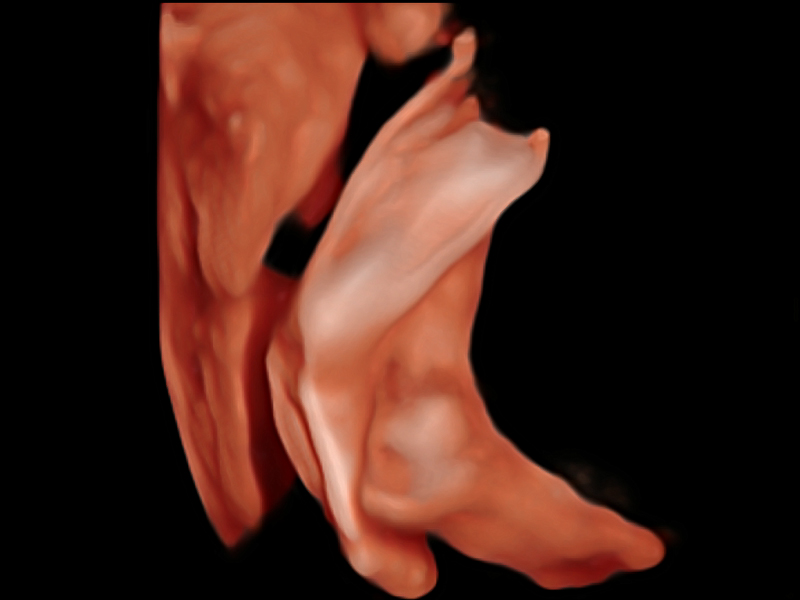

S-Fetus基于大数据深度学习算法,能够帮助您在产前筛查过程中智能识别胎儿标准切面、自动测量并录入报告。一个按键,即可智能、精准、高效地获取胎儿生理指标,极大简化您的产科检查操作。

可快速对产科扫查切面完成胎儿生理学参数的自动测量,减少操作者按键次数,大幅提升检查效率。

自动识别颈项透明层并获得NT值,为早孕胎儿畸形筛查提供有效测量工具,提高诊断效率和诊断信心。